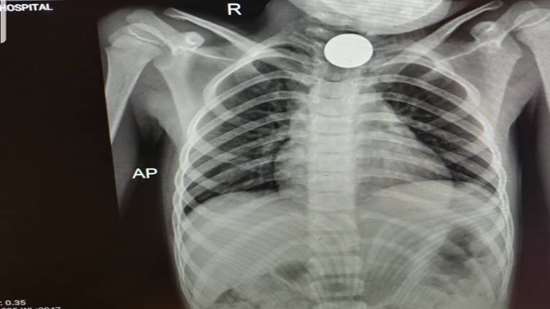

امکان عمل جراحی خروج اجسام خارجی از حلق و مری کودکان با خريد دستگاه ازوفاگوسكوپ رژید در بیمارستان رازی شهرستان سراوان

با خريد و نصب دستگاه ازوفاگوسكوپ رژيد در بیمارستان رازی سراوان امکان عمل جراحی خروج اجسام خارجي بلعيده شده در حلق و مری كودكان يا بزرگسالان میسر گردیده است.

دکتر محمد قره بیگلو، رئیس بیمارستان رازی سراوان با اشاره به اینکه روند عمل جراحی خروج اجسام خارجی بلعیده شده در حلق، گلو يا مري کودکان به دلیل خطرات جانی باید بصورت اورژانسی صورت گیرد خاطر نشان کرد: گاها در شهرستان سراوان به دلیل این اتفاق کودکان را به مرکز استان اعزام می کردیم ولی در حال حاضر با نصب و راه اندازی دستگاه ازوفاگوسكوپ رژید خوشبختانه امکان عمل جراحی خروج اجسام خارجی از گلو و حلق کودکان فراهم گردیده است.

وی نصب و راه اندازی این دستگاه را بدلیل پیشگیری از خطرات جانی کودکان، حرکتی بزرگ در عرصه سلامت سراوان برشمرد و افزود: برای خرید و تجهیز این امکانات 600 میلیون ریال هزینه گردیده است.